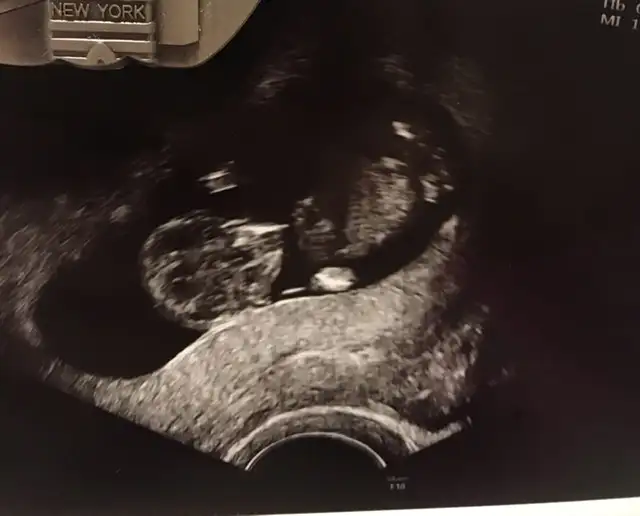

Bugün doktora gittik ama yüzüstü yatıyordu bir şey göremedik :))) siz keseye bakıp erkek, 12. Haftaya bakarak kız demiştiniz. Şimdi 17. Haftadayız:) ben erkek hissediyorum dedim doktor bence tam tersi sanki dedi 😁 sizce ne olabilir Ikra meyra Ikra meyra

• 1A39E66F-0510-49FE-A176-6E30CDF80312.webp

1A39E66F-0510-49FE-A176-6E30CDF80312.webp

26,4 KB · Görüntüleme: 55

12 de Kız tahmin etmiştim hale kız diyorum